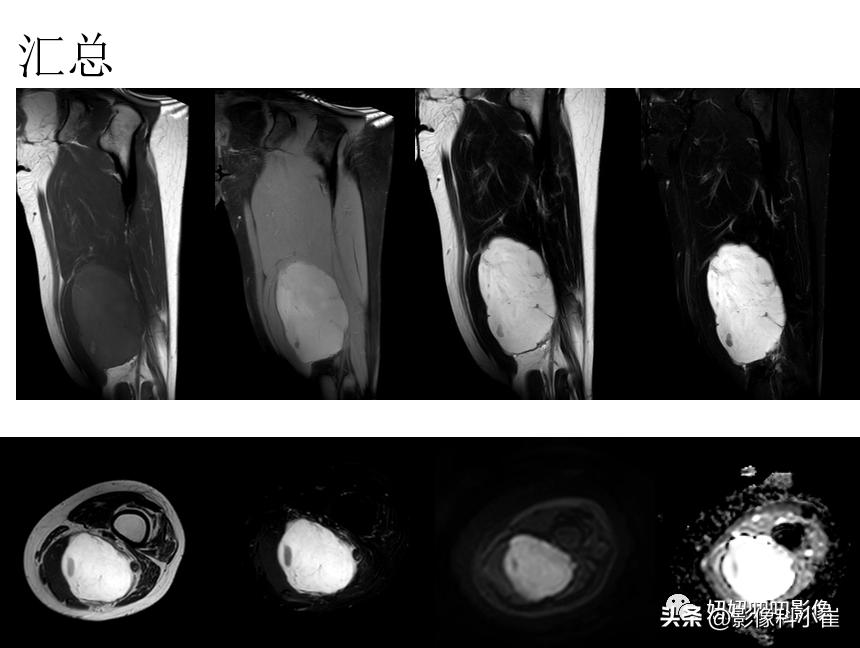

老师总结:

①:病理都是粘液样脂肪肉瘤;

②:思路流程:

先看与骨头的关系,是否骨源性;

再看软组织是肌内(纤维类多见)的还是肌间隙的?

肌肉间隙的话:脂肪?滑膜(1钙化大2侵犯骨头3信号混杂)?神经(梭形)?脉管?